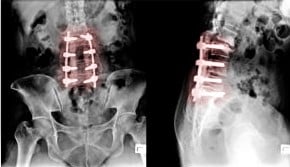

首や腰の背骨に金属が入っておられる方、膝や股関節に人工関節をいれておられる方など。

また、当院では、レントゲンを詳しくみて、分析することでより安全にカイロプラクティックケアを行うことができます。

詳しい検査とレントゲン分析で「みる」ことにより、なんとなくの施術がなくなります。

金属部分や人工関節部へは、直接施術は行いません。

それ以外のところにカイロケアをしてゆくことで、身体はしっかりと改善してゆきます。